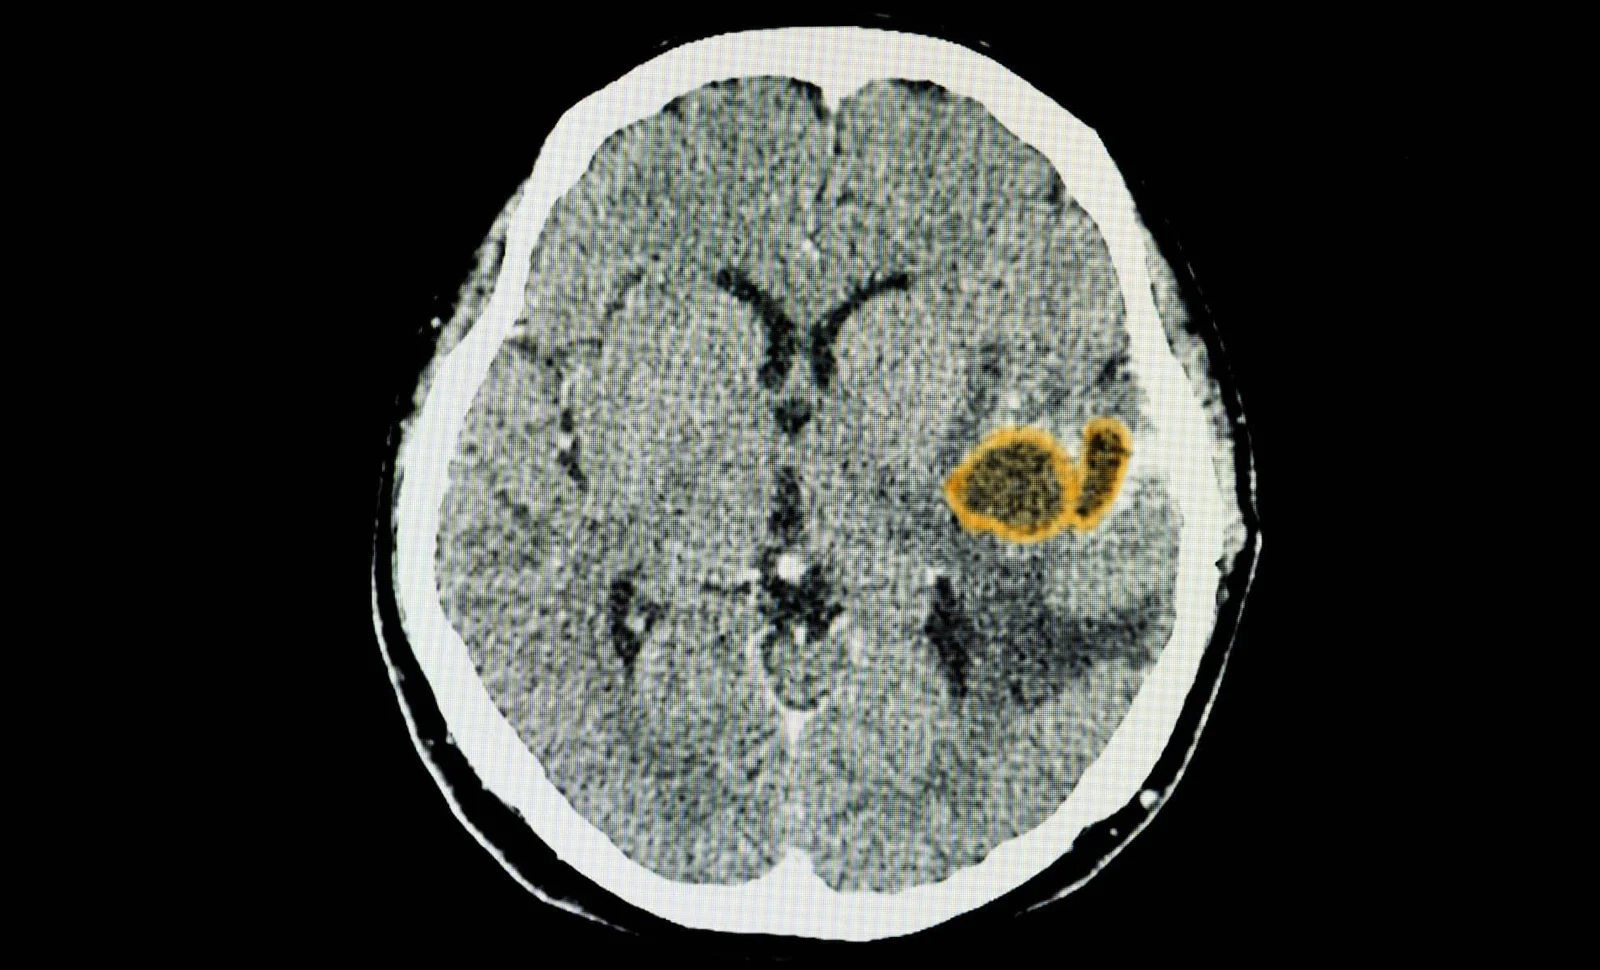

Brain Parasite Toxoplasma gondii Is Stopped by Immune Cells' Self-Destruct Switch

Researchers at UVA Health found that the brain parasite Toxoplasma gondii can infect CD8+ T cells, but these immune cells use the enzyme caspase-8 to trigger a self-destruct mechanism that kills the infected cell and the parasite inside. In mice lacking caspase-8 in their T cells, brain parasite levels were higher and outcomes worse, indicating caspase-8 is crucial for limiting brain infection. With about a third of people believed to carry T. gondii, most cases are asymptomatic, though toxoplasmosis remains a risk for the immunocompromised. The study, published in Science Advances, enhances understanding of how the immune system controls the parasite and why T cells’ self-destruction can prevent brain persistence.